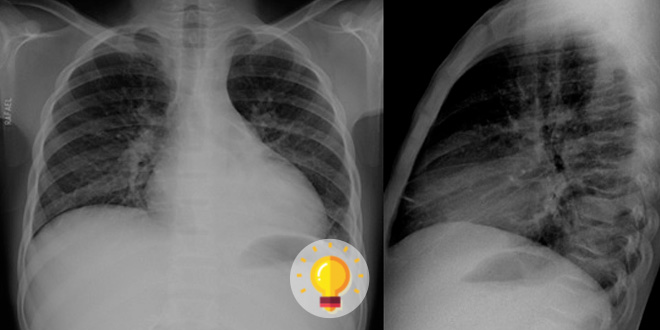

Raio X Torax Normal X Covid

Imaging The Coronavirus Disease Covid 19

Normal Chest X Ray Doesn T Rule Out Covid 19

The Radiology Assistant Covid 19 Imaging Findings